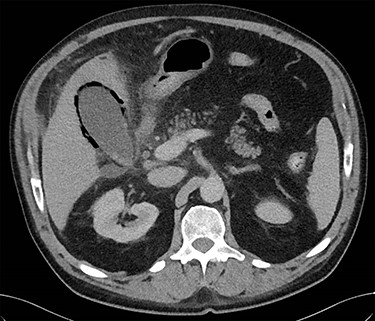

On presentation to the emergency department, the patient was tachycardic and febrile and his serology showed a neutrophilia, elevated CRP and bilirubin with normal hepatic transaminases. On examination, he was focally tender with voluntary guarding in the right upper quadrant. A CT abdomen was performed which identified a distended gallbladder, with adjacent gas locules and fat stranding around the hepatic flexure. The differentials included a contained microperforation at the hepatic flexure or emphysematous cholecystitis. The patient was haemodynamically stable and therefore a period of non-operative treatment was pursued. The patient was commenced on IV ampicillin, metronidazole and gentamicin, strict fluid balance, nil by mouth with regular clinical reviews. On Day 3, the patient had shown minimal clinical improvement and a progress CT was obtained which revealed extensive gas within the gallbladder wall and adjacent-free fluid consistent with emphysematous cholecystitis (Figs 1 and 2).